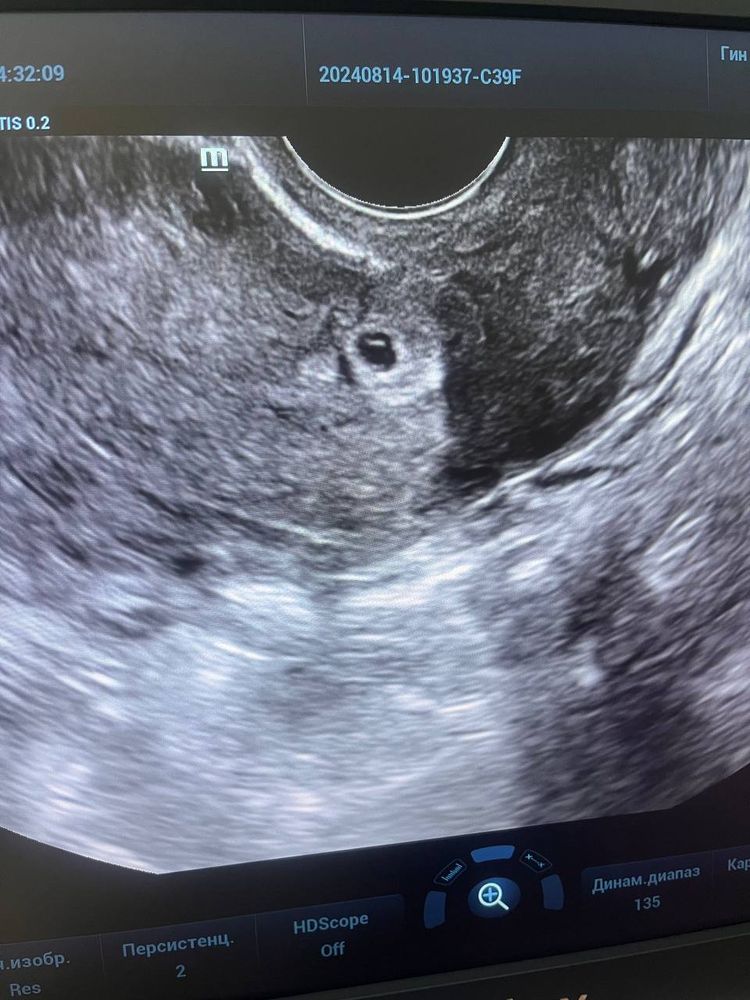

Беременность 3 недели кровит